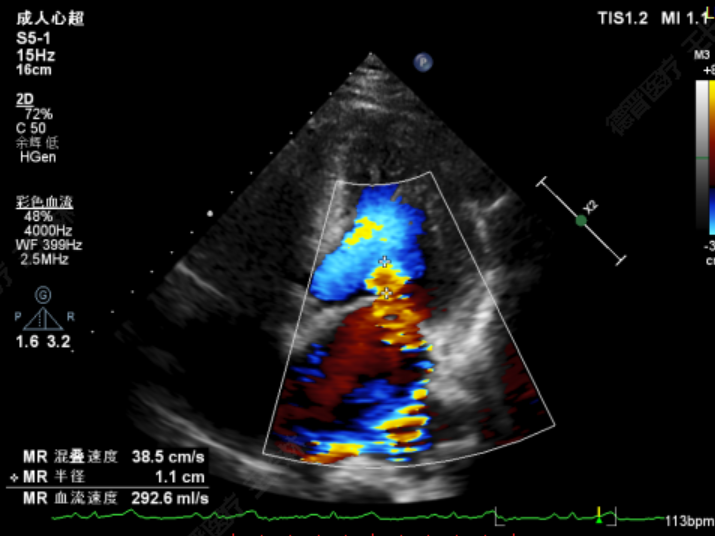

患者全麻后在超声和射线引导下穿刺股静脉-房间隔,器械顺利到达病变的二尖瓣区域,成功完成二尖瓣夹合后,患者二尖瓣反流即刻显著下降,左房压力即刻减低,预示着患者的临床症状将会得到明显改善。